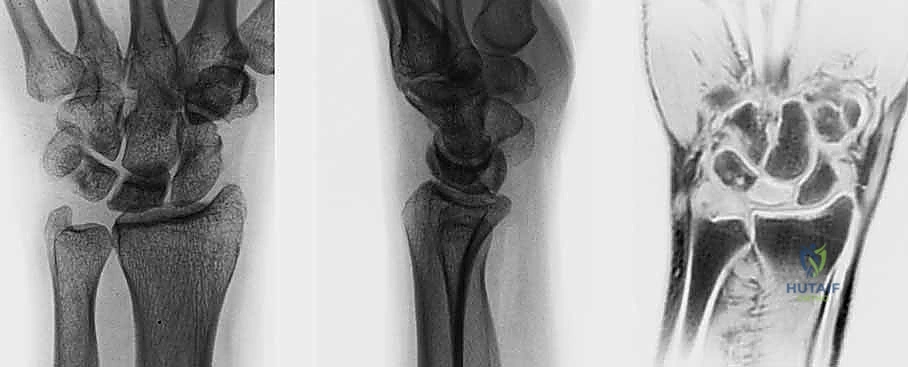

- الأشعة السينية (X-rays): هي الخطوة الأولى. في المراحل المبكرة جداً، قد تظهر الأشعة السينية طبيعية تماماً. في المراحل اللاحقة، يظهر العظم الهلالي بلون أبيض ناصع (متصلب)، ثم يبدأ في الظهور مفلطحاً أو متفتتاً.

- التصوير بالرنين المغناطيسي (MRI): هو المعيار الذهبي للتشخيص المبكر. يمكن للرنين المغناطيسي اكتشاف نقص التروية الدموية (وذمة العظم) قبل أشهر من ظهور أي تغيرات في الأشعة السينية. يعتمد الدكتور هطيف بشكل كبير على الرنين المغناطيسي لتحديد مرحلة المرض بدقة.

- التصوير المقطعي المحوسب (CT Scan): يُستخدم لتقييم مدى تفتت العظم الهلالي وبنيته ثلاثية الأبعاد، وهو أمر حاسم في التخطيط الجراحي.

مراحل ليختمان (Lichtman Classification) لمرض كينبوك

يُصنف المرض عالمياً باستخدام نظام ليختمان، وهو دليل أساسي يحدد مسار العلاج:

| المرحلة الأولى (Stage I) | أشعة سينية طبيعية. ألم خفيف. الرنين المغناطيسي يظهر نقص التروية. العظم محتفظ بشكله. | علاج تحفظي (تثبيت) أو تدخل جراحي بسيط لتحسين التروية. |

| المرحلة الثانية (Stage II) | الأشعة السينية تظهر العظم الهلالي أكثر بياضاً (تصلب). العظم لا يزال محتفظاً بشكله العام ولكن قد تظهر خطوط كسر دقيقة. | جراحة لتفريغ الضغط أو زراعة طعم وعائي. |

| المرحلة الثالثة أ (Stage IIIA) | انهيار وتفلطح العظم الهلالي. تفتت الأجزاء. لا يوجد انهيار في ارتفاع عظام الرسغ الكلية. | زراعة طعم عظمي وعائي + جراحة تسوية المفصل (تقصير العظم الكبير أو تطويل الكعبرة). |

| المرحلة الثالثة ب (Stage IIIB) | انهيار العظم الهلالي مع انهيار ارتفاع الرسغ وانحراف العظم الزورقي. ميكانيكا الرسغ مضطربة. | دمج جزئي لعظام الرسغ (Partial Wrist Arthrodesis) أو استئصال الصف القريب. |

| المرحلة الرابعة (Stage IV) | انهيار كامل للرسغ مع تطور خشونة متقدمة (التهاب مفاصل) في المفاصل المجاورة. | دمج كلي للرسغ (Total Wrist Arthrodesis) أو استبدال المفصل. |